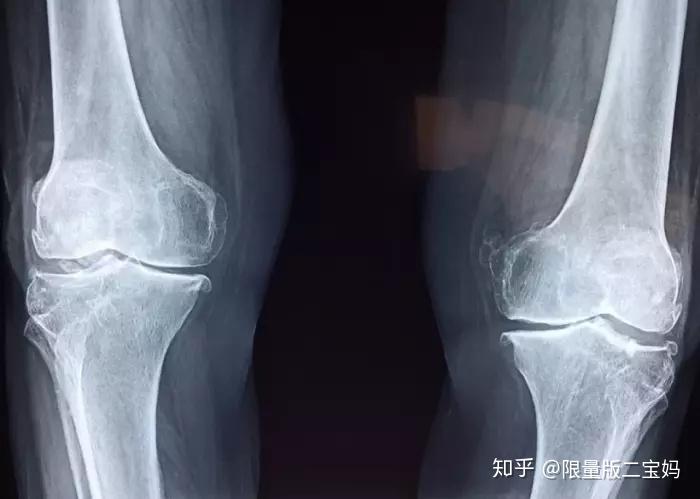

氨糖与骨关节炎

全球 60 岁以上的人中,10% 的男性和 18% 的女性都受到骨关节炎的困扰 [1]。

目前骨关节炎没有特别好的根治疗法,治疗上以止痛和提高生活质量为主,在非常严重的情况下会考虑关节置换手术。

但随着年龄增长,软骨逐渐磨损退化,于是骨头两端就会硬性摩擦,导致各种关节疾病。

英国医学杂志《柳叶刀》报道过硫酸氨糖治疗膝部骨关节炎——随机、双盲、安慰剂对照的临床研究,结果显示硫酸氨糖有明显疗效,且减缓了关节破坏的进展。